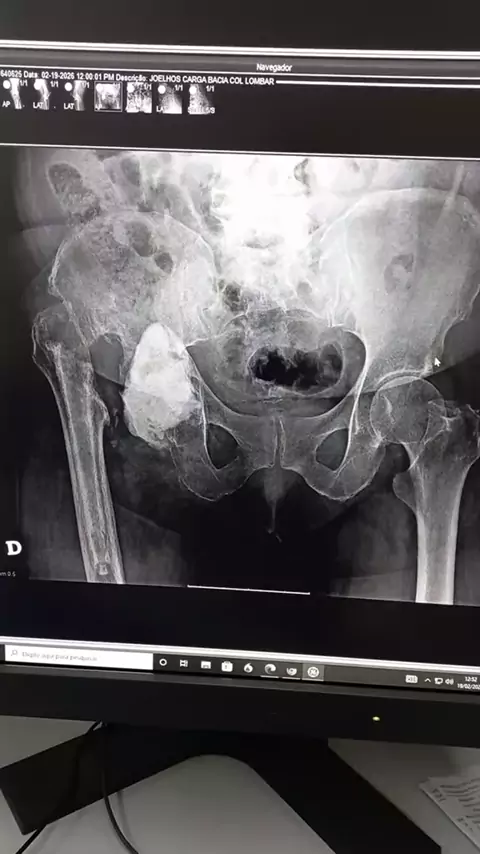

Desgaste no quadril, artroplastia total e complicações que resultou na retirada do implante ☢️ #artroplastia #desgaste #artrose #quadril #ortopedia